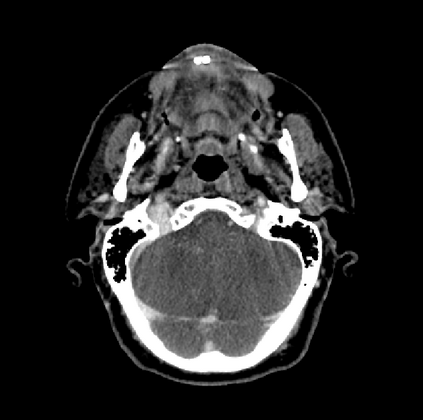

Organ at risk (OAR) segmentation is a critical process in radiotherapy treatment planning such as head and neck tumors. Nevertheless, in clinical practice, radiation oncologists predominantly perform OAR segmentations manually on CT scans. This manual process is highly time-consuming and expensive, limiting the number of patients who can receive timely radiotherapy. Additionally, CT scans offer lower soft-tissue contrast compared to MRI. Despite MRI providing superior soft-tissue visualization, its time-consuming nature makes it infeasible for real-time treatment planning. To address these challenges, we propose a method called SegReg, which utilizes Elastic Symmetric Normalization for registering MRI to perform OAR segmentation. SegReg outperforms the CT-only baseline by 16.78% in mDSC and 18.77% in mIoU, showing that it effectively combines the geometric accuracy of CT with the superior soft-tissue contrast of MRI, making accurate automated OAR segmentation for clinical practice become possible. See project website https://steve-zeyu-zhang.github.io/SegReg